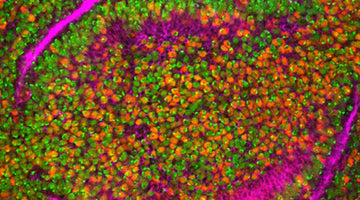

Publication Spotlight: A Mouse Model of SARS-CoV-2 Infection and Pathogenesis

Check out how researchers are using HUABIO antibodies to advance discovery.